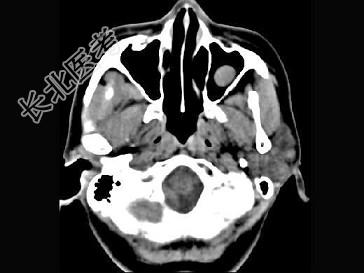

- 单项选择题男,7岁, 无明显症状,CT如图所示, 最可能的诊断是 ( )

A、上颌窦淋巴瘤

B、上颌窦炎

C、上颌窦黏膜下囊肿

D、上颌窦乳头状瘤

E、鼻炎及副鼻窦黏膜下囊肿